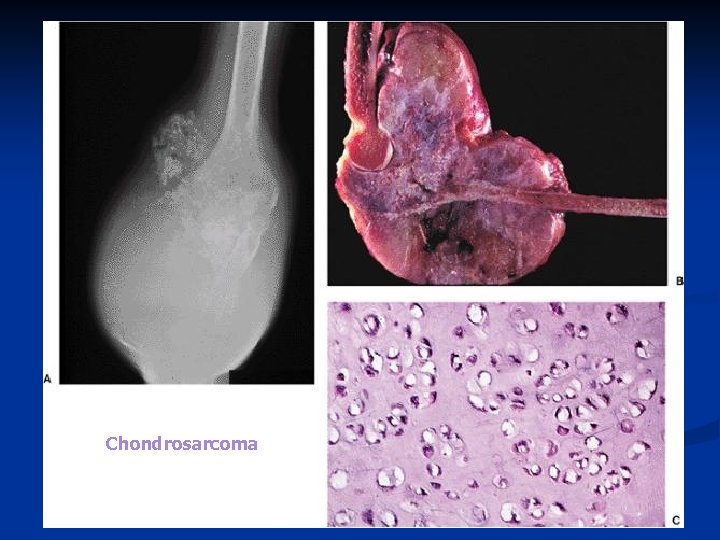

Chondrosarcoma A malignant cartilaginous tumor n The third to sixth decades of life (average of 45 years) n Slightly more common in males than females n

n Chondrosarcoma may originate in the medullary cavity (central chondrosarcoma) n n about 75% of cases or by malignant transformation of a preexisting enchondroma particularly in patients with enchondromatosis, May originate in a juxtacortical location (peripheral chondrosarcoma) by sarcomatous change in the cartilage cap of an osteochondroma.

n Location: n flat bones of the pelvis n the large limb bones n femur 25% n humerus n the ribs

n Radiology: Radiolucencies (irregular or circular or bubbly) n Calcification (granular or lobular radiopaque areas) n Destruction of the inner cortex, n Enlargement of bone contours, n Focal periosteal reaction, n Penetration of the cortex. n

Chondrosarcoma

Chondrosarcoma

Chondrosarcoma

n Microscopy a lobular cartilaginous architecture, n highly cellular, n more than one nucleated cell per lacuna, n occasionally reveals tumor giant cells or clear cells, n with increasing grades of malignancy, has marked variation in nuclear and cellular size and shape. n

Chondrosarcoma